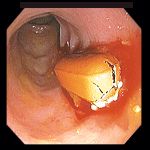

- 38-летний человек потерял сознание в аэропорту. Установлена передозировка наркотических средств. При обзорной рентгенографии брюшной полости обнаружены инородные тела толстого кишечника.

- При колоноскопии были обнаружены капсулы, заполненные наркотическим веществом (на фото удаление капсулы петлей).

- На фото видны 13 капсул из общего количества, составившего 31 капсулу.